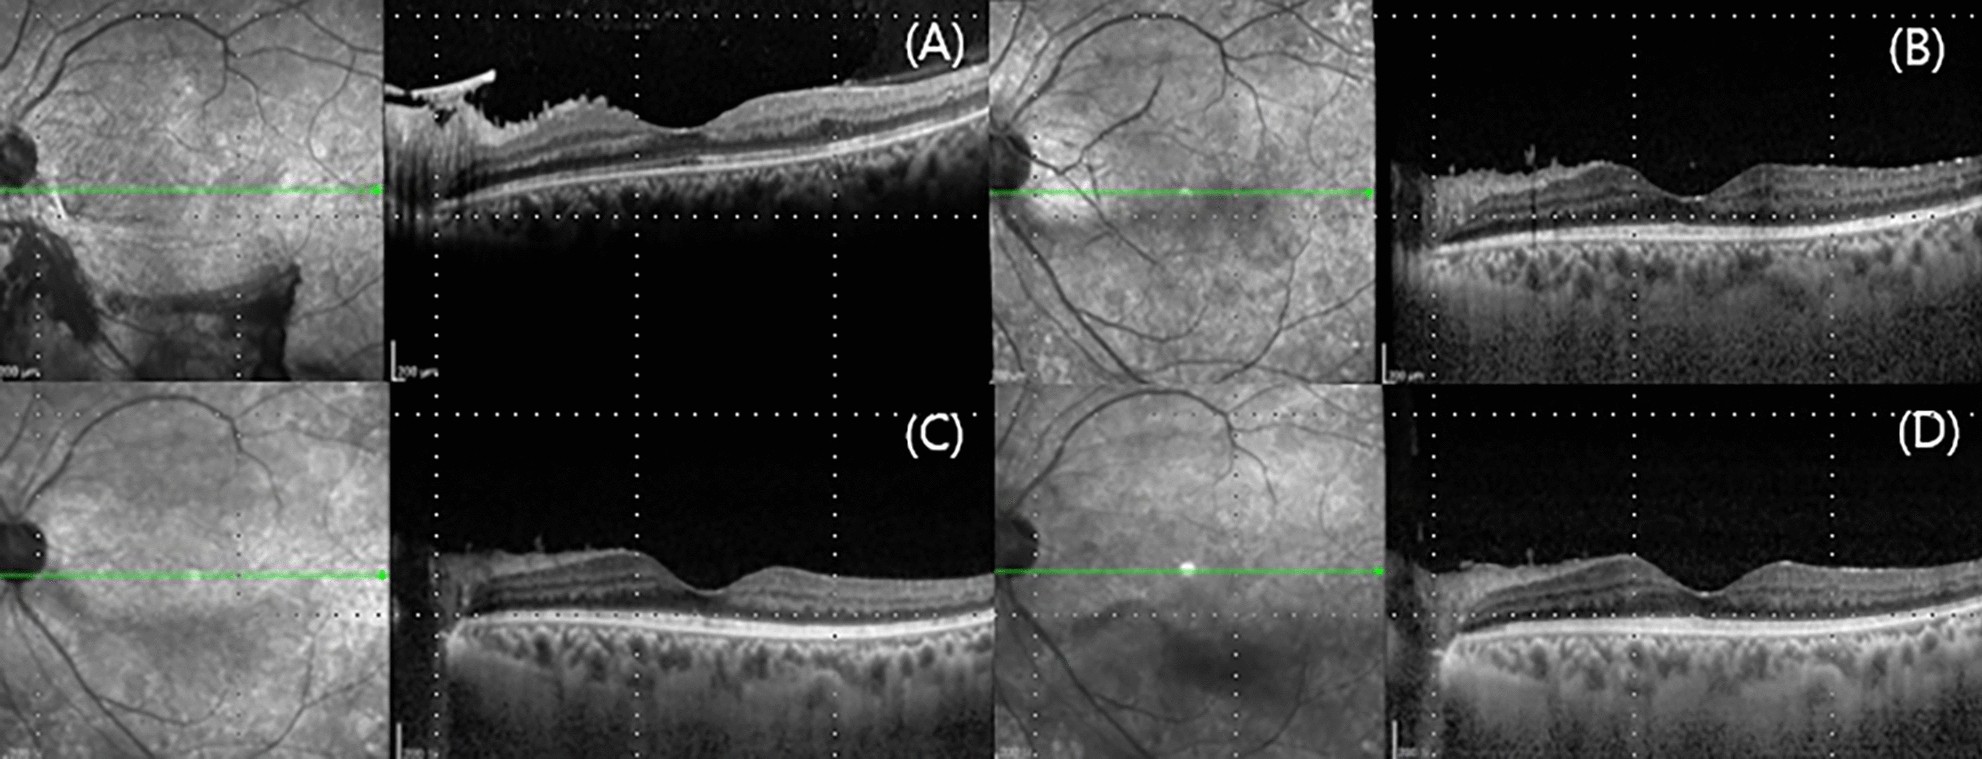

Figure 4

Optical coherence tomography of case 1 at (A) initial visit, (B) 24 months, (C) 48 months, and final visit. No diabetic macular edema developed during the follow-up period.